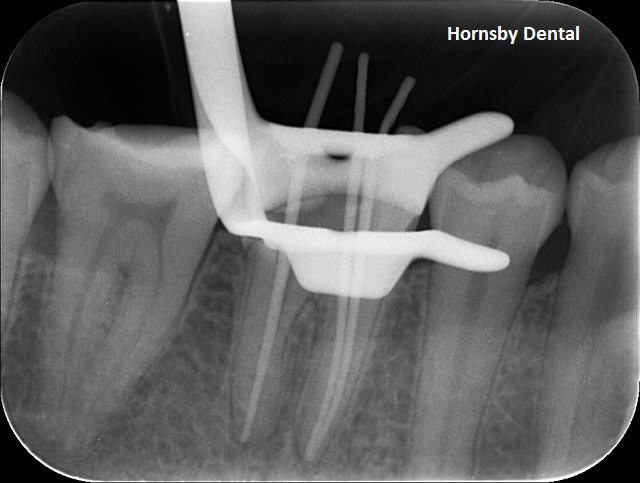

MEASUREMENT

Measurement: The root canal therapy is essentially the treatment to rid infection inside the pulpal/nerve space within the tooth, and to seal the tooth from further reinfection into the root tip of the root. This needs to be performed very carefully and should always have a “rubberdam” isolation field to avoid the re-introduction of bacteria from within the mouth into the canal spaces. Without rubberdam, the treatment is considered compromised. In this image the dentist has used a clamp to lock the rubberdam to the tooth and is measuring the sealing length for the final root filling.